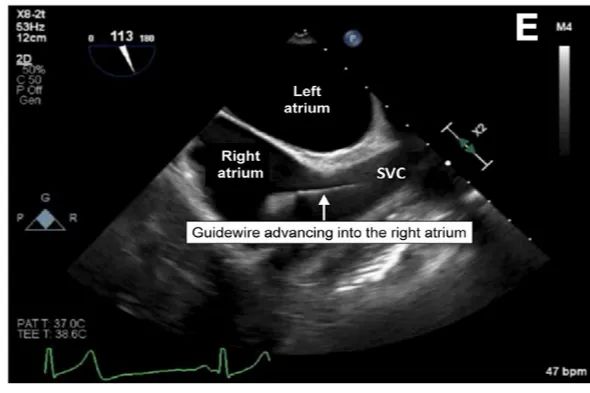

经食管超声心动图(TOE)可以可靠地确认导丝在SVC和RA中的位置、静脉通路的部位(图E)。在起搏器导线、先前存在的导管或扭曲心脏或食管解剖异常的情况下,用食道超声确认导线或导管可能很困难。与透视一样,在CVC放置过程中支持常规使用食道超声的证据有限,但国际社会指南推荐它作为替代技术。